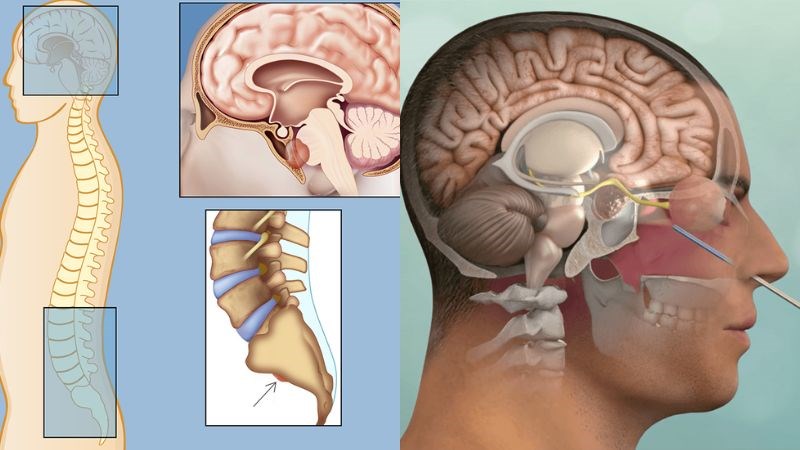

U nguyên sống (Chordoma)

U nguyên sống là bệnh lý ác tính hiếm gặp, tiến triển chậm, phát triển từ phần tồn dư của dây sống, vì vậy u có thể gặp ở mọi vị trí của trục xương sống mà phần lớn là ở 2 đầu: mặt dốc xương đá (clivus) và xương cùng (sacrum).

Độ tuổi thường gặp: U nguyên sống thường xuất hiện ở nam giới độ tuổi 40 – 60.

U nguyên sống là bệnh lý ác tính hiếm gặp và thường tiến triển chậm